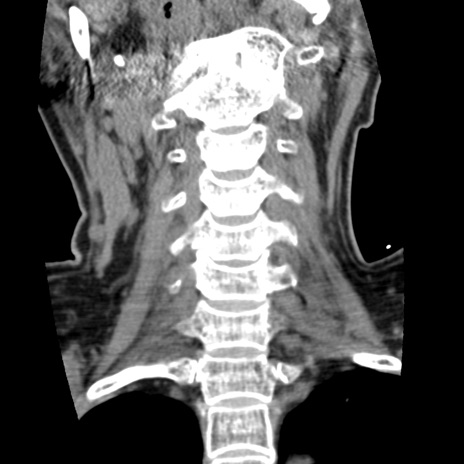

症例50 頚椎CT(冠状断像)

【症例】60歳代女性

【主訴】後頭部〜右後頸部にかけての痛み

【現病歴】本日飲食店でコーヒーを飲んでいたところ、突然後頭部〜右後頸部にかけて痛みが出現し、右上肢の感覚障害を伴ったため救急要請。

【身体所見】脳神経学的に明らかな異常所見を認めず。右上肢に軽度の感覚障害あり。

異常所見と診断は?

頚椎CT